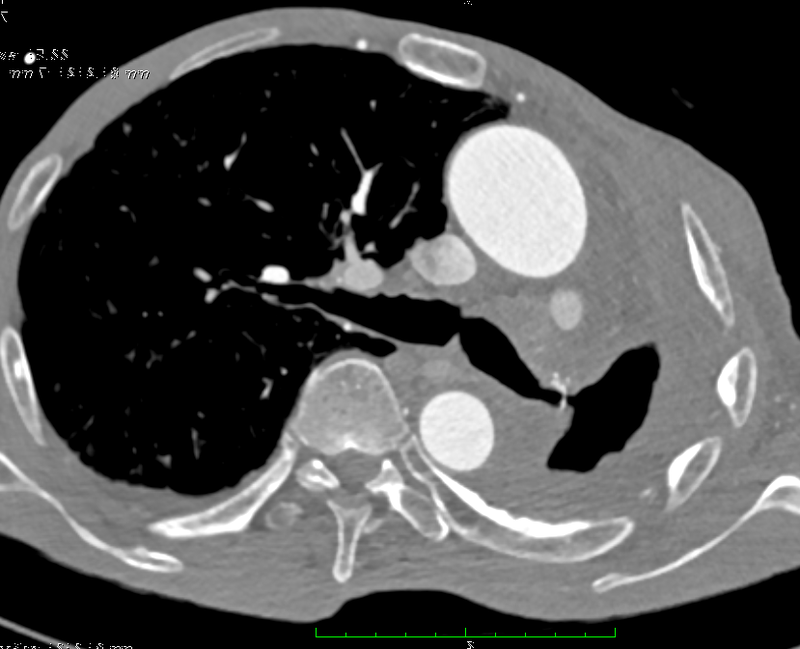

66歲男性,有吸煙病史。2年多前行左側(cè)全肺切除,術(shù)后并發(fā)支氣管胸膜瘺。2年多來,患者和家屬四處求醫(yī),6次進(jìn)行介入封堵,均告失敗。最近一次,左側(cè)主支氣管瘺口的封堵器脫位,磨破食管,穿入食管,造成支氣管食管瘺,感染更加嚴(yán)重,進(jìn)食食物從膿胸引流管中流出。患者惡病質(zhì),嚴(yán)重消瘦,體重從手術(shù)前的65公斤下降到49公斤。手術(shù)使用腹腔鏡,微創(chuàng)獲取帶血管蒂大網(wǎng)膜,轉(zhuǎn)移到胸腔,修補(bǔ)瘺口,填塞膿腔。封堵手術(shù)一次成功,患者1周開始正常進(jìn)食,胸部腹部外觀基本正常,功能正常,沒有開窗術(shù)或胸廓成形術(shù)的恐怖外觀和功能殘疾。隨訪9個月,患者正常飲食,體力完全恢復(fù)。支氣管胸膜瘺本就是胸外科的巨大難題,支氣管胸膜瘺合并支氣管食管瘺-胸膜瘺,惡病質(zhì)患者,罕見成功救治病例。本方法有較大優(yōu)勢:成功率高:大網(wǎng)膜抗感染能力強(qiáng),治愈BPF成功率高,本例一次性封閉支氣管瘺口和食管瘺口即是明證;微小創(chuàng)傷,術(shù)后外觀、功能正常:因?yàn)榇缶W(wǎng)膜強(qiáng)大的抗感染能力,故不需要大范圍的胸壁塌陷或是胸壁開窗換藥,沒有胸壁開窗術(shù)和胸廓成形術(shù)帶來的恐怖外觀和功能殘疾。